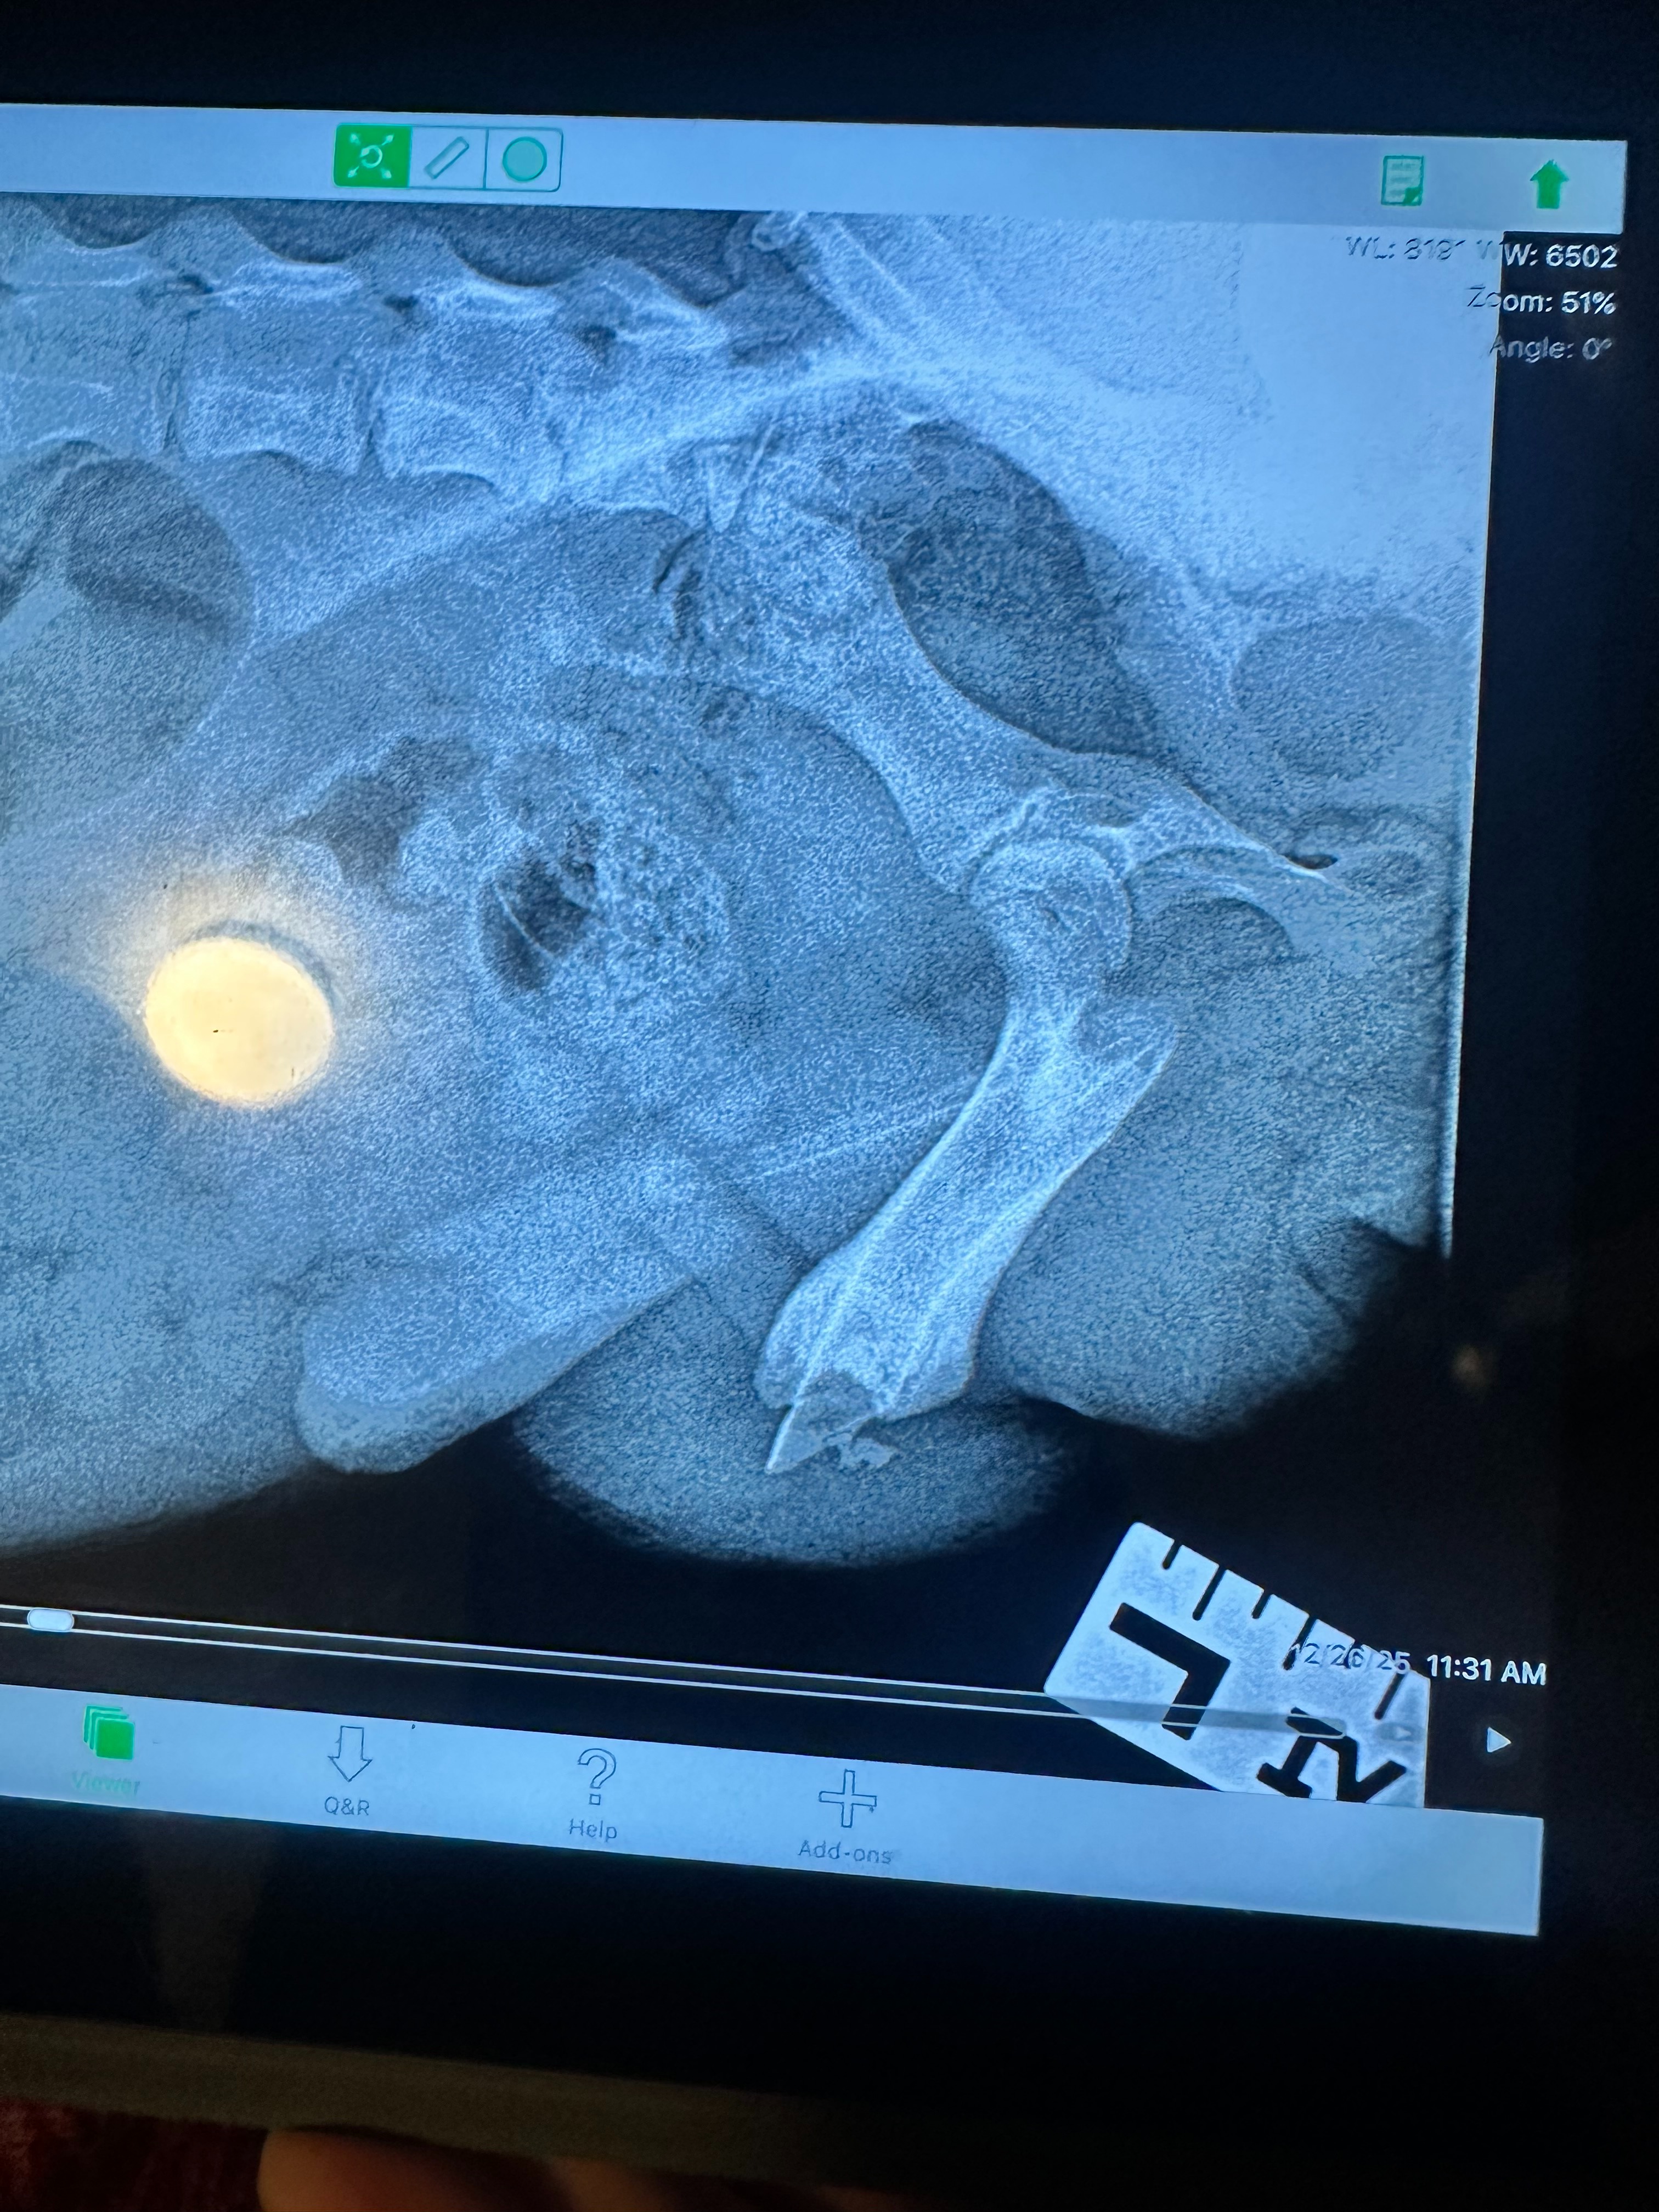

Tragically, on Christmas Day, Tommy’s incision began to reopen and seep fluid. We were so thankful that the people at Plum Creek Veterinary Services were able to get us in right away on December 26, where devastating news was discovered: Tommy was the victim of a botched amputation. Bones and bone fragments were left behind at the amputation site, including one sharp point that is causing him pain and preventing proper healing. He now urgently needs a second corrective surgery so he can heal fully and live without discomfort.

Today, we learned that in addition to his negligent amputation, he also had post-surgical complications that have left him with a mass in his leg likely comprised of clotted blood and fibrous tissue. That will need to be removed in addition to the remainder of his femur and any bone fragments.